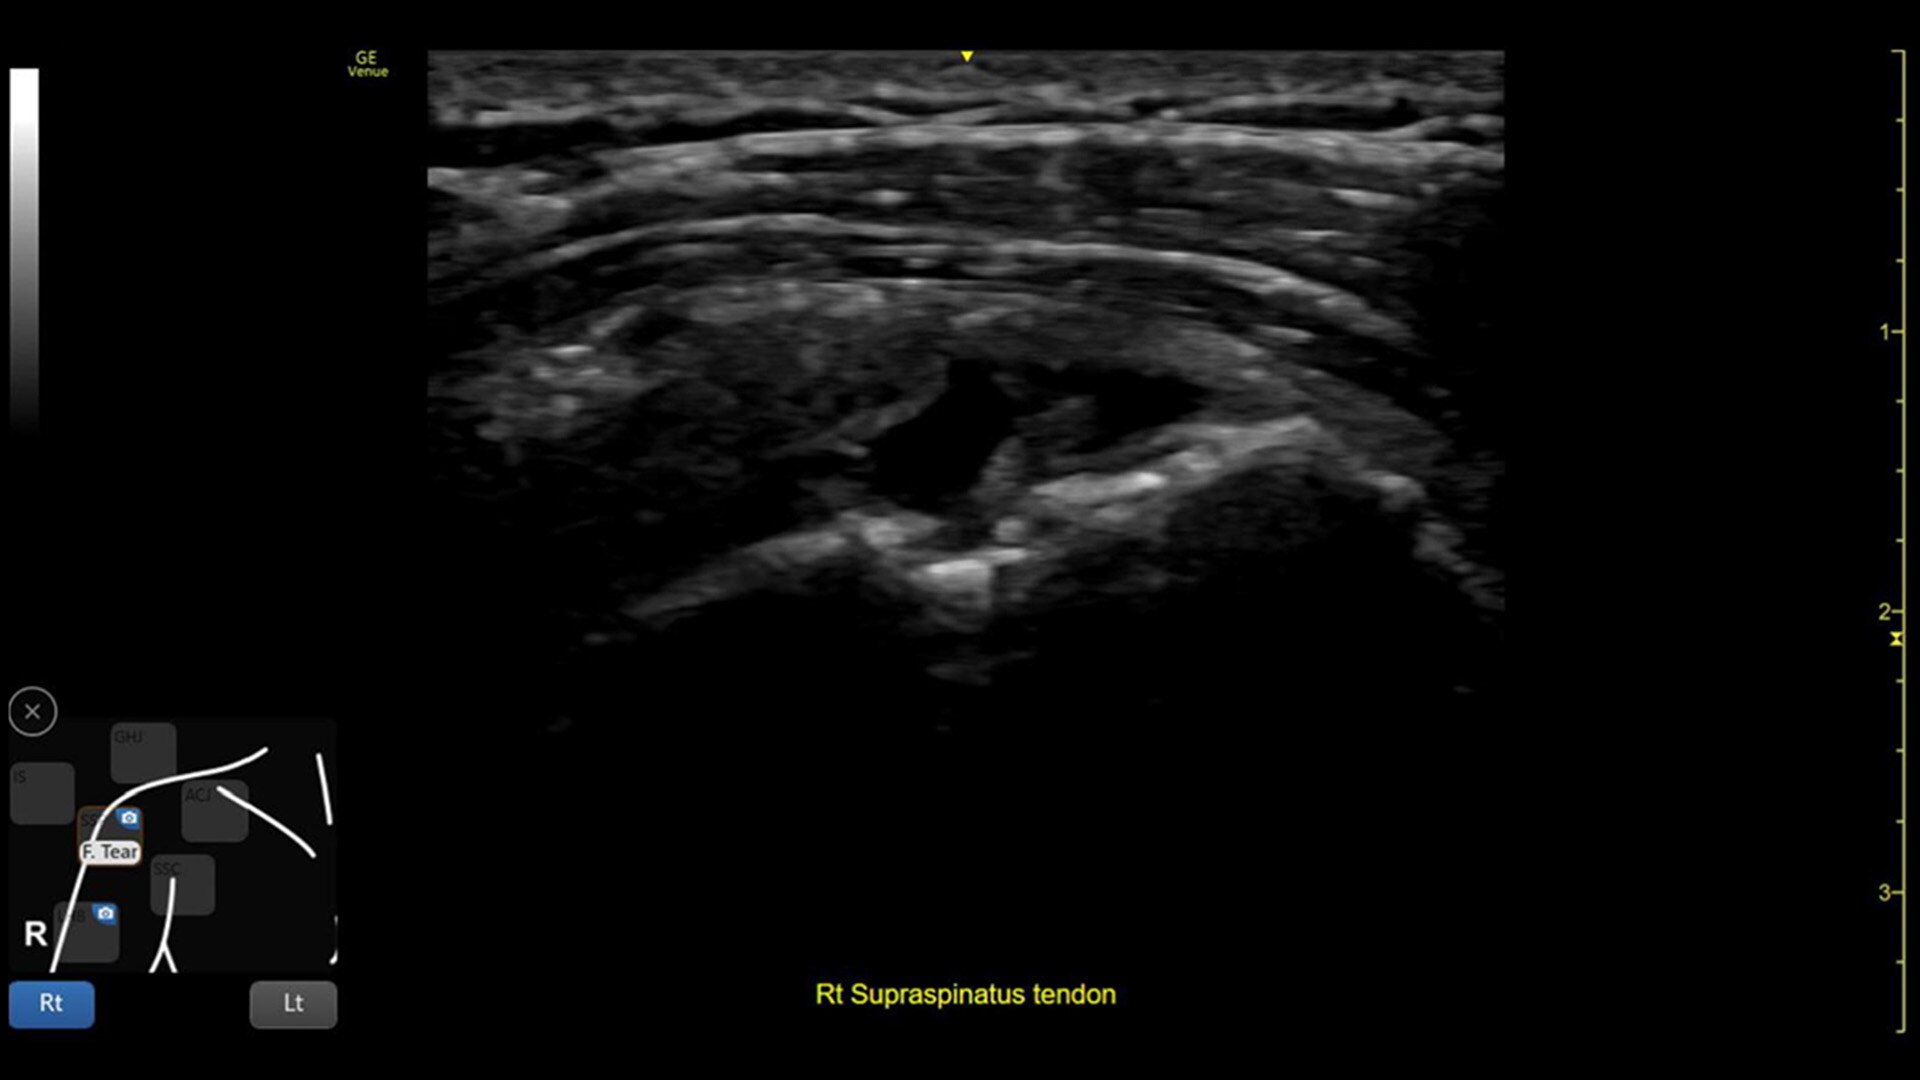

• MSK Diagrams: Simplifies documentation and assists the clinician in follow up for patients. No need to manually type findings—you can simply assign a label from a pre-populated list that correlates with the images. Get a single view diagram with one click image storing, keep track of assessments and show trends in response to therapy.

• Reference Image: Reference image provides anatomy mark-ups to assist novice users in scanning the correct anatomy

• Bilateral mode: Helps you to view the opposite side of the same zone for comparison (available for Shoulder preset)